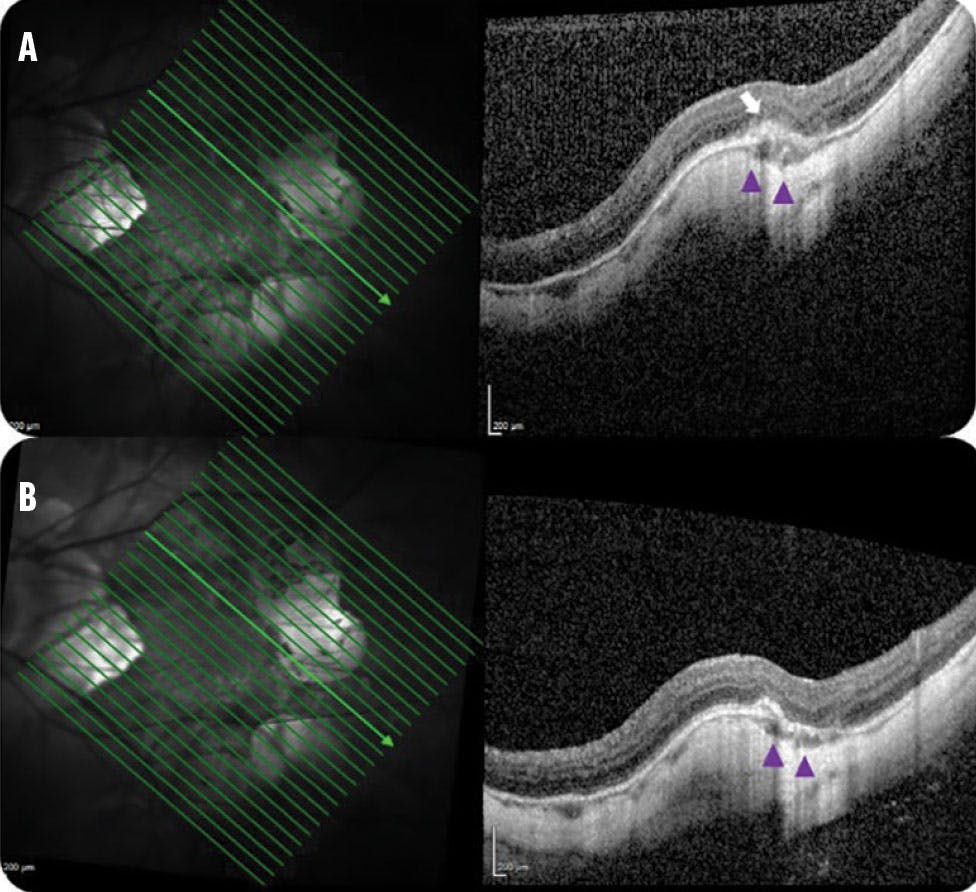

Another challenge with myopic MNV is the detection of exudation, which is more subtle than in other types of MNV.10 Clinicians can look for the presence of a gray subretinal hyperreflective exudation and an increase in choroidal thickness (Figure 4). In these cases, a single anti-VEGF injection can address subretinal hyperreflective exudation and decrease the choroidal thickness underneath the myopic MNV.

<p>Figure 4. Exudative recurrence, represented by gray subretinal hyperreflective exudation, of a previously treated myopic MNV (A, white arrow) with an increase in choroidal thickness (purple arrowheads). After one anti-VEGF injection (B), OCT shows regression of the subretinal hyperreflective exudation, as well as a decreased choroidal thickness.</p>

Figure 4. Exudative recurrence, represented by gray subretinal hyperreflective exudation, of a previously treated myopic MNV (A, white arrow) with an increase in choroidal thickness (purple arrowheads). After one anti-VEGF injection (B), OCT shows regression of the subretinal hyperreflective exudation, as well as a decreased choroidal thickness.

After studying the morphologic relationship between myopic MNV activity and focal choroidal thickness changes in pathologic myopia during anti-VEGF therapy, researchers found that focal choroidal thickness increased significantly underneath the myopic MNV when exudative signs were present (or preceding exudation in some cases), followed by a significant decrease after anti-VEGF therapy.11